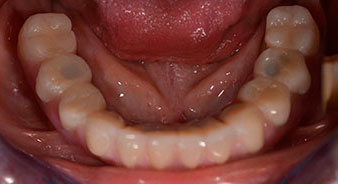

A three-dimensional cone beam computed tomography scan (CBCT, Planmeca) was performed to aid planning and minimize risks. This revealed that the quality and quantity of the available bone were sufficient for the surgery and immediate restoration using the Fast & Fixed method. Following the protocol for this concept, the implants are inserted at 35, 32, 42 and 45. Angling the distal implants by up to 45° shifts the emergence profile to posterior and generates a larger support polygon (Fig. 3).